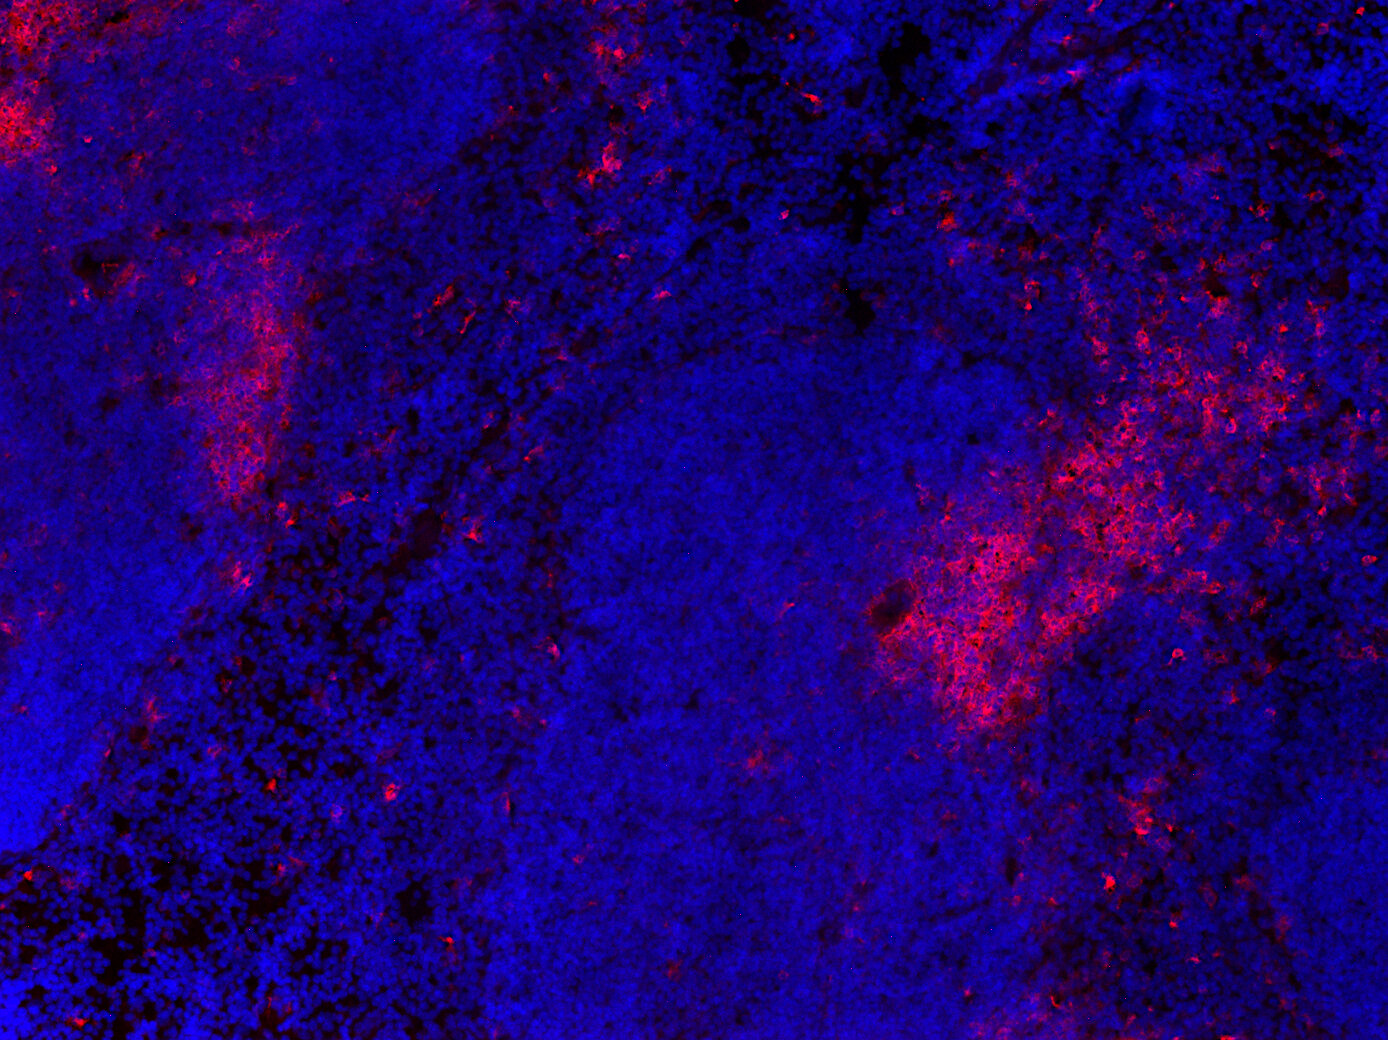

CD11c positive cells in FFPE mouse ileum section

IHC: 1 : 500 (see remarks) gallery

IHC-P: 1 : 50 up to 1 : 100 gallery

IHC-Fr: 1 : 500 (see remarks) gallery

Immunohistochemistry (IHC) on 4% PFA perfusion fixed tissue with 24h PFA post fixation. Immunoreactivity is usually revealed by fluorescence or a chromogenic substrate. Some antibodies require special fixation methods or antigen retrieval steps. For details, please refer to the ”Remarks” section.

Immunohistochemistry (IHC-P) of formalin fixed, paraffin embedded (FFPE) tissue (some antibodies require special antigen retrieval steps, please refer to the ”Remarks” section). Immunoreactivity is usually revealed by fluorescence or a chromogenic substrate.

Immunohistochemistry on fresh frozen (IHC-Fr) cryo-tissue-sections. In contrast to standard PFA perfusion fixed tissues, fresh frozen cryo-tissue-sections can be variably postfixed with alcohols, acetone or PFA. Alcohol or acetone fixation is e.g. of advantage for antigens masked by PFA crosslinking. For recommended postfixation, please refer to the ”Remarks” section. Immunoreactivity is usually revealed by fluorescence or a chromogenic substrate.

IHC: Antigen retrieval with citrate buffer pH 6 is required.

IHC-Fr: 4% formaldehyde/PFA fixation is recommended.